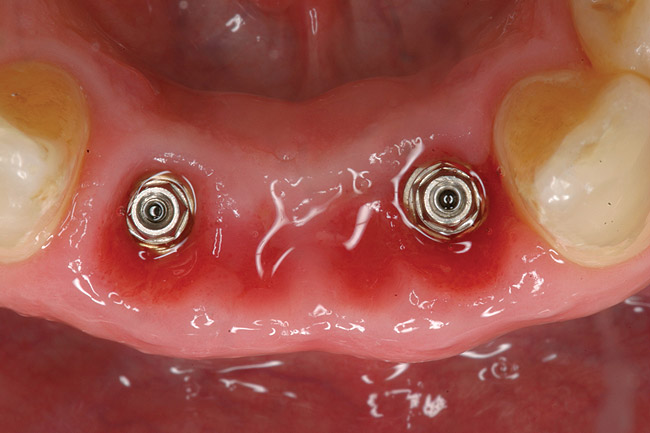

Figure 1  Preoperative clinical condition.

Figure 1